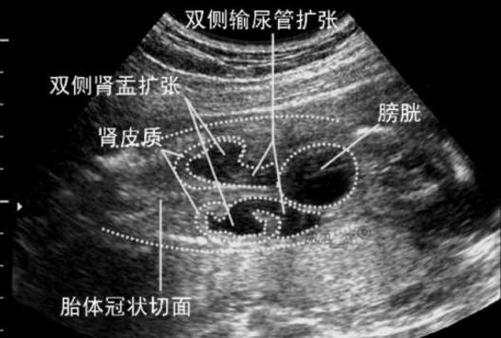

肾盂是肾脏中汇集尿液的“漏斗”部分,当尿液在肾脏内产生后,需要通过肾盂、输尿管、膀胱排出体外,如果排尿的某个环节暂时有点“堵”,或者因为憋尿等原因,尿液在肾盂里稍微积聚多一些,就会导致肾盂看起来比平时“宽”,这就是肾盂分离。

(图片来源网络,侵删)- 憋尿: 这是最主要的原因,在做B超检查时,宝宝可能刚好因为各种原因(如被包裹、环境陌生等)没有排尿,导致膀胱充盈,尿液排出不畅,肾盂内压力增高,出现暂时的分离,5mm的分离量非常小,很可能就是一次憋尿造成的。

- 新生儿输尿管蠕动功能不协调: 新生儿的输尿管肌肉还比较娇嫩,其节律性的蠕动(将尿液从肾脏推向膀胱的功能)可能不够成熟和有力,偶尔会出现轻微的“拥堵”现象,导致肾盂暂时性扩张。